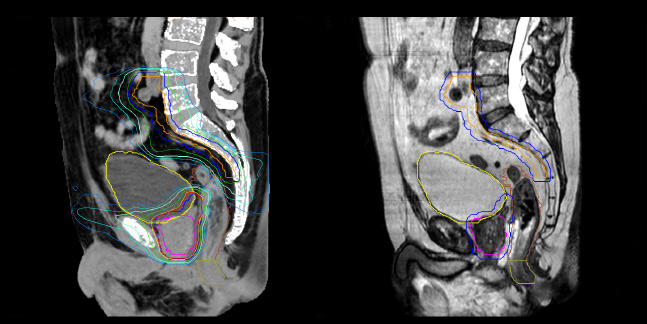

Dataset MRCAT image

Dose plans overlaid on CBCT image dataset (left) and on MRCAT image dataset (right).

Evaluation of MRCAT dosimetric accuracy

Dosimetric equivalence validation was performed on 43 patient cases by comparing MRCAT-based dose plans overlaid on CBCT image dataset and on the corresponding MRCAT image dataset. Mr. Bolard and Dr. Champion found good agreement between MRCAT-based and CT-based dose calculations, with a mean dose ratio of 1.007 (0.991-1.014). The 3D gamma score was greater than 95% (95.2-99.0%) for all plans checked. A poster on this work was accepted for presentation at ESTRO 2020.

MR-based contouring and planning

MRCAT is primary image dataset for dose calculation (left).

3D T2W TSE MRI with 36 cm Field-of-View is used for delineation of prostate and organs at risk (right).